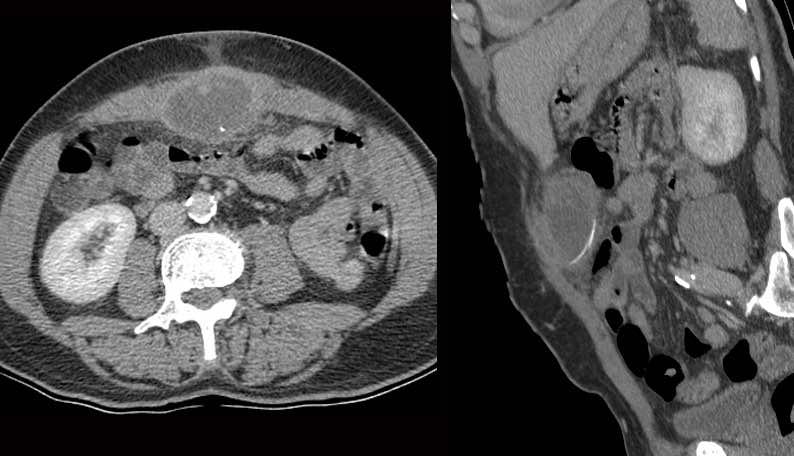

Bệnh nhân nam 53 tuổi nhập viện với khối đau hố chậu trái và CRP 173, nghi ngờ viêm túi thừa.

Bệnh nhân có tiền sử cắt thận trái 20 năm trước.

Siêu âm phát hiện áp xe thành bụng chứa một cấu trúc mỏng, đường cong (mũi tên).

CT không và có tiêm thuốc cản quang tĩnh mạch xác nhận xương cá (mũi tên) trong áp xe thành bụng có ranh giới không rõ ràng.

Lưu ý rằng xương cá có thể dễ dàng bị bỏ sót nếu chỉ chụp CT có tiêm thuốc cản quang tĩnh mạch.

Vị trí áp xe và xương cá được đánh dấu trên da.

Chỉ với một đường rạch rất nhỏ, mủ và xương cá đã được lấy ra. Hồi phục không biến chứng.

Bệnh nhân nam 57 tuổi (tiền sử cắt ruột thừa) với nghi ngờ viêm túi thừa.

CT cho thấy dày thành đại tràng sigma (s.) và một khối không rõ ràng ở phía trái.

Tại thời điểm này, đường tăng âm nhỏ (mũi tên) đã bị bỏ sót.

Chẩn đoán CT là viêm túi thừa đại tràng sigma hoặc ác tính đại tràng sigma.

Nội soi đại tràng không tiếp cận được vùng này.

Trên CT lặp lại một tuần sau, chúng tôi may mắn khi dị vật sắc nhọn thẳng và hơi tăng âm (mũi tên) lần này hiện ra toàn bộ chiều dài trên CT mặt phẳng coronal.

Trong phẫu thuật, một phần đại tràng sigma được cắt bỏ cùng với một khối viêm lớn, chứa que tăm cocktail bằng gỗ là nguyên nhân gây bệnh.

Một hậu môn nhân tạo tạm thời đã được tạo ra.

Bệnh nhân tỏ ra không tin và kiên quyết phủ nhận việc đã nuốt phải que đó.